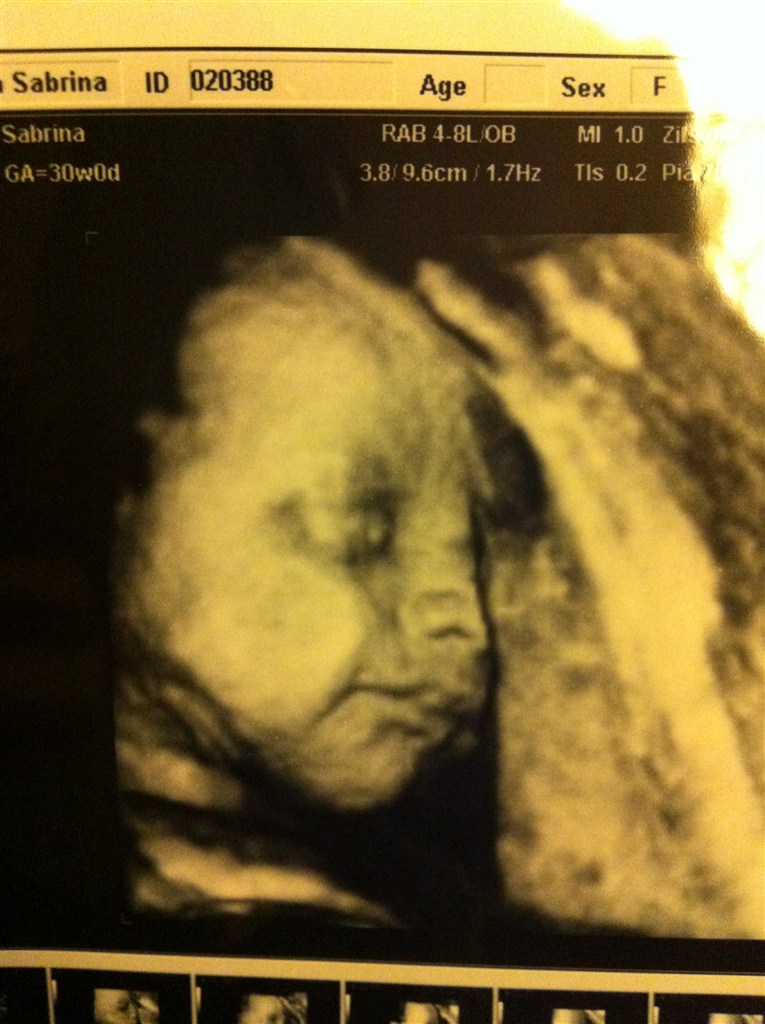

Jeg ved seriøst heller ikke hvad jeg skal med alle de billeder - tror jeg vil gøre som Michelle skrev tidligere, ligge dem i en kasse med andre ting fra graviditeten - og så kan vores datter få den når hun bliver stor